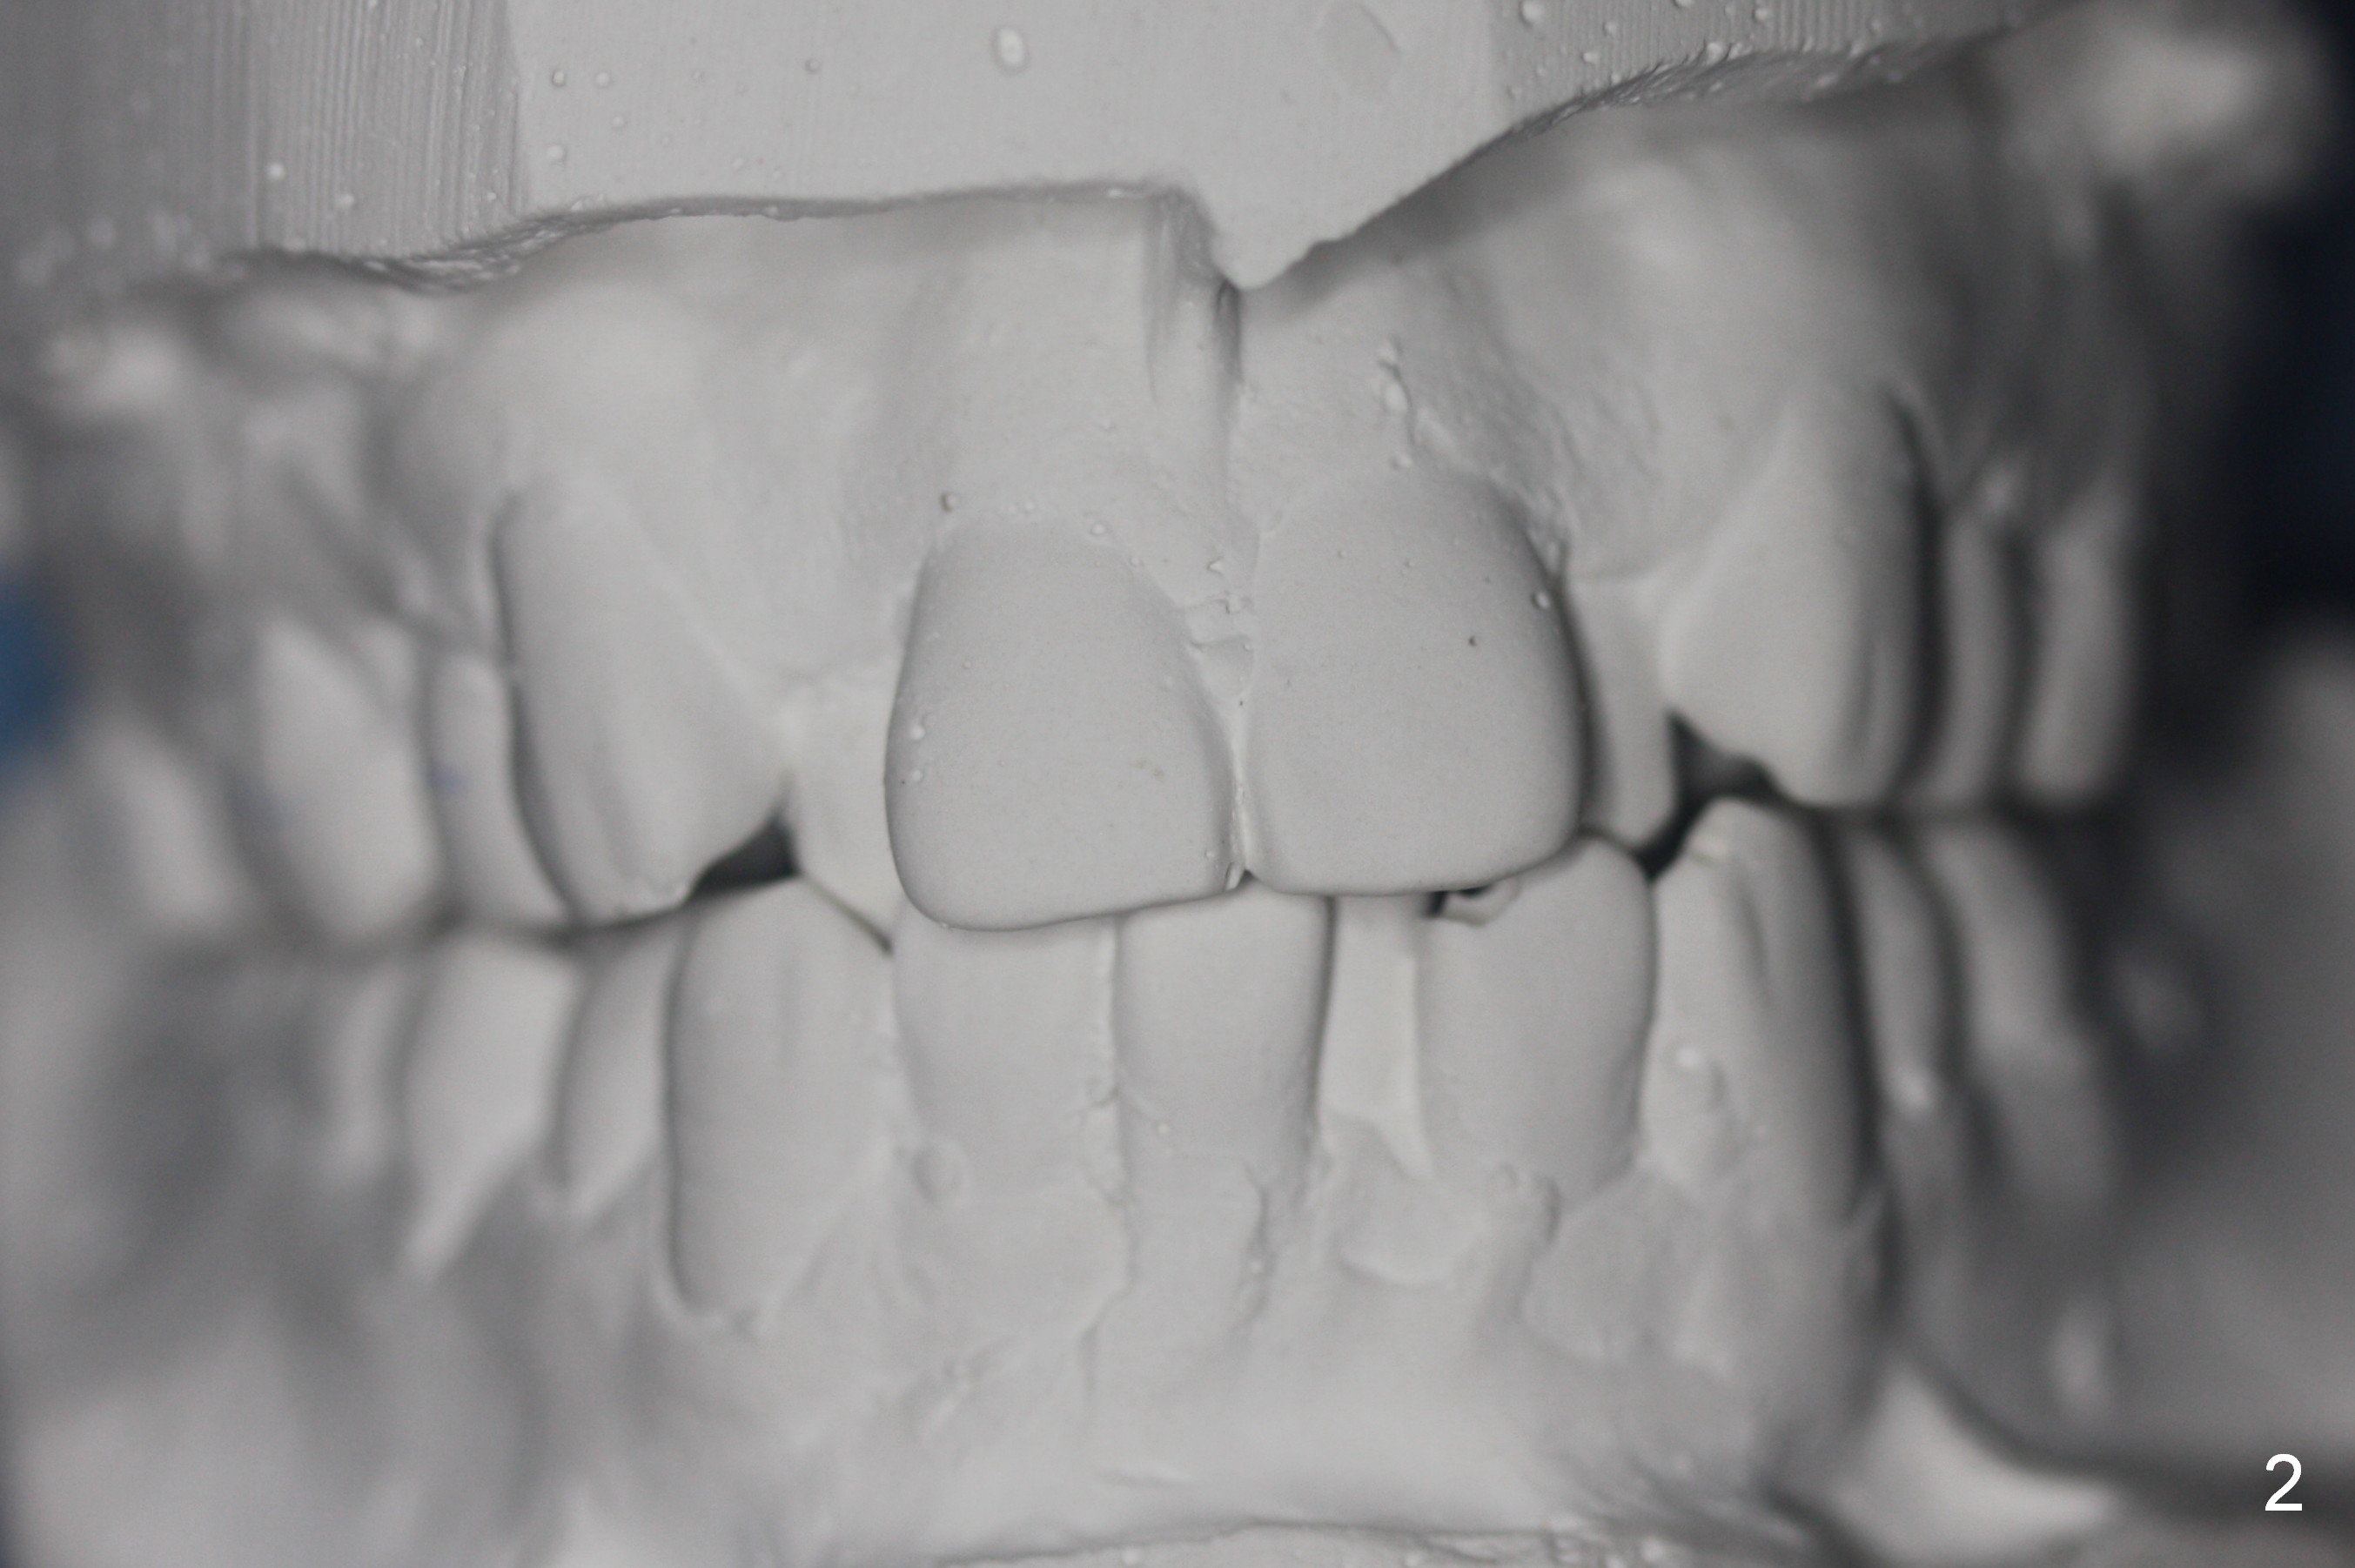

A 37-year-old man requests orthodontic treatment for severe crowding with 3 blocked-out incisors (Fig.1-5: 12,22,31 (International numbering, pronounced one two, two two and three one)). The upper and lower arches are pointed (Fig.4,5). The best option is extraction of 4 bicuspids (Fig.11-15).

His profile is convex with lip strain. After alignment of the anterior teeth, check the facial profile to determine whether it is necessary to distalize the anterior teeth or not. If it is, the distalization will be done with the aid of an implant at 47 (Fig.1,5 (residual roots)) and 3 mini-implants at the 3 other quadrants. An extra mini-implant will be placed at the upper right quadrant to intrude 17 (Fig.1 arrow).